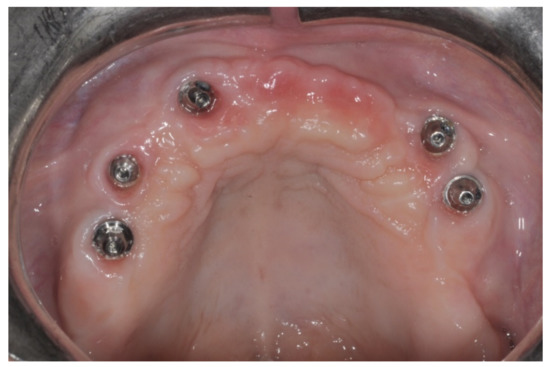

After surgery, the same antibiotic treatment was continued thrice a day for 3 days. Analgesics (ibuprofen 600 mg) were suggested to the patient to be taken twice a day during meals on demand. A soft diet was recommended until the removal of the sutures. Patients were recalled weekly for the first month and thereafter monthly to monitor the tissue healing. Patients were instructed to avoid brushing the surgical site and to rinse with 0.12% chlorhexidine mouthwash until the removal of the sutures, which was 12 days after the augmentation. After 8 to 9 months, healing screws were connected to the implants, which were surgically exposed (Figure 14).

Figure 14. Occlusal view after 9 months of healing showing the newly regenerated bone.